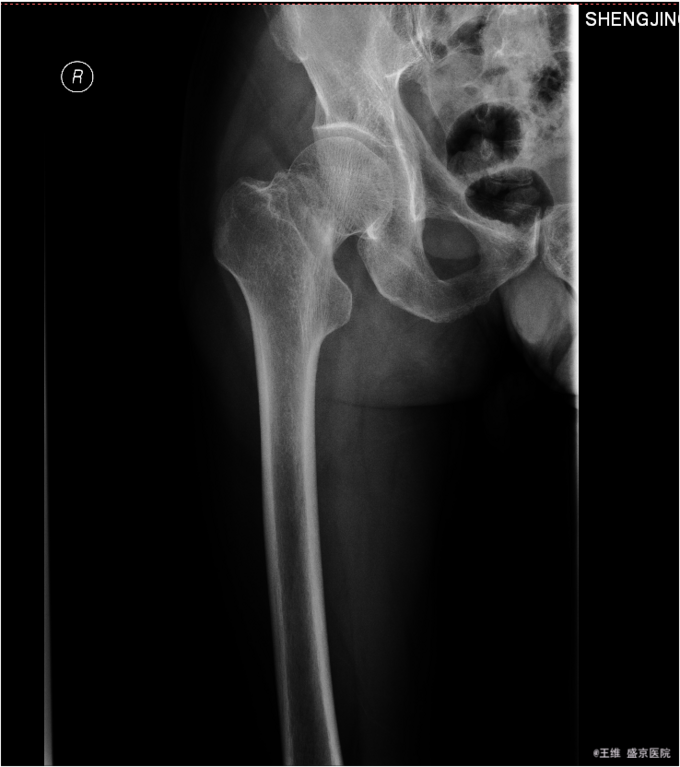

1.患者男性,67岁,以“摔伤后右髋部疼痛肿胀活动受限5小时”为主诉入院。 2.现病史:患者及家属自述于2015年12月17日在沈阳市骑车时被机动车刮碰后摔倒,后自觉右髋部疼痛肿胀活动受限,摔倒后无昏迷。遂被急送至我院急诊,急诊行骨盆CT示:右股骨颈骨折。现患者以“右股骨颈骨折”为诊断收入我科。患者病来,意识清楚,自诉无头晕头迷,恶心呕吐,无咳嗽咳痰,无心慌气短,饮食正常,二便正常,体重无变化。

专科查体:右髋部肿胀,未见明显瘀斑,活动度减低。右髋部压痛阳性,叩击痛阳性,右下肢缩短畸形,缩短3cm,外旋畸形,外旋60°。右膝及右踝关节活动无明显异常。双侧足背动脉搏动有力,肢体末梢血运良好,皮温正常。远端足趾感觉运动正常。 辅助检查:骨盆三维CT:右股骨颈骨折

诊断:右股骨颈骨折(Garden IV型) 患者入院后完善相关检查后,择期性右全髋关节置换术,术后患者脚穿矫正鞋,外展中立位,术后3天后患者自动退院,